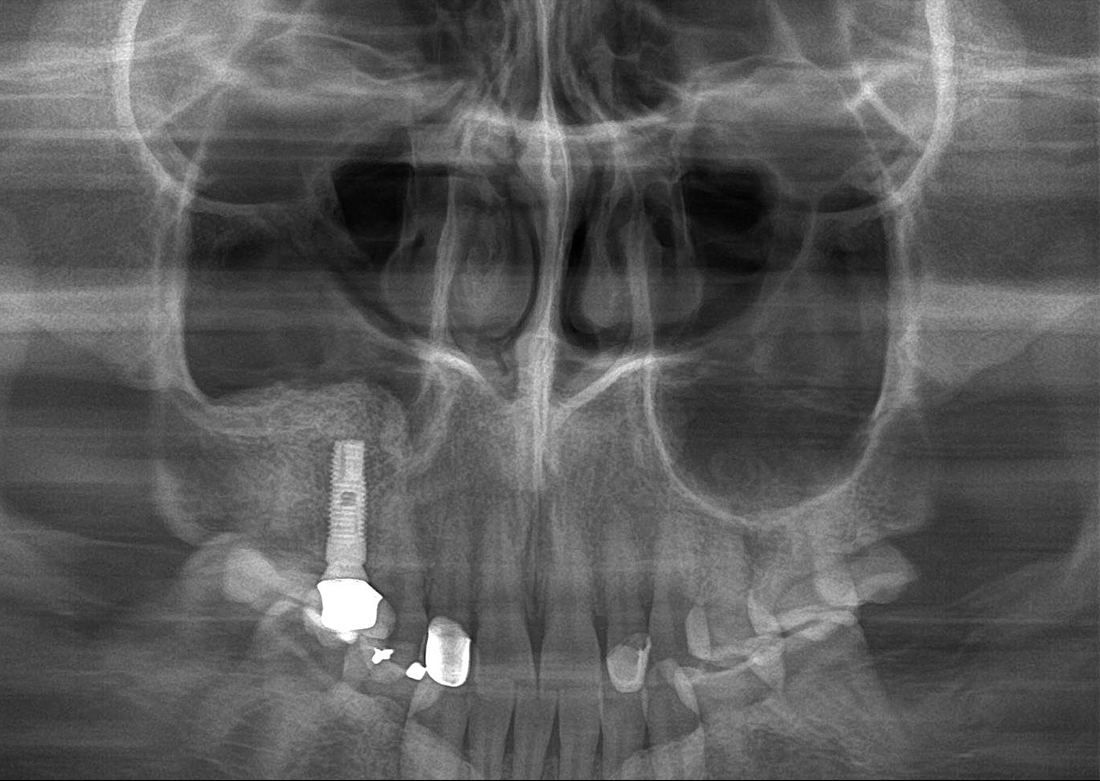

KLİNIKAI KÉPEK

Kiváló diagnosztikai képalkotás több éves tapasztalattal és szakértelemmel.

A Genoray büszkesége, amelyet világszerte elismernek és szeretnek.